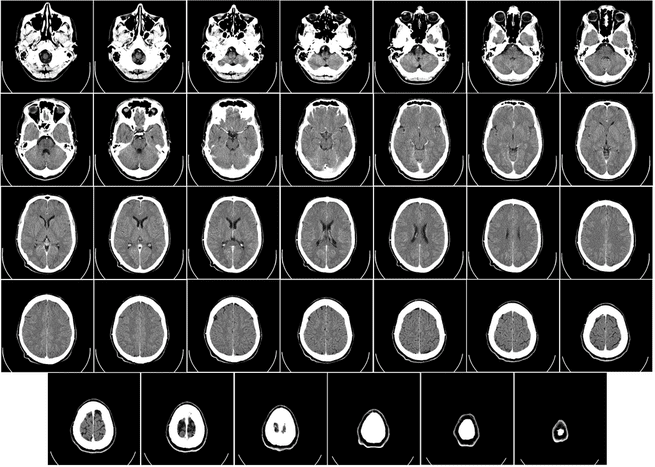

مصدر الصورة: ويكيميديا كومونز